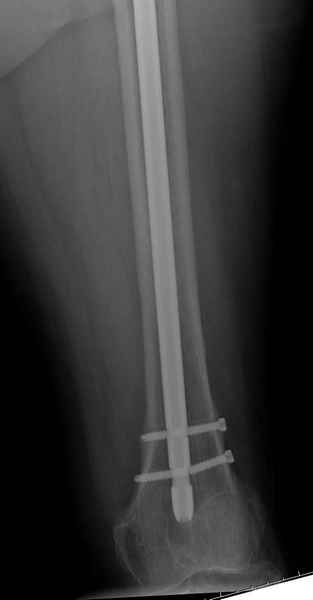

Михаил, здравствуйте. Если присмотреться - на четвертом снимке есть перелом гвоздя по отверстию.

Видимо, проблем тут две: во-1-х, центральный отломок был оставлен в варусно-сгибательной установке, во-2-х, не динамизировали вовремя.

Нижние винты хотели сломаться, но, увы, один не сломался, и тогда сломался гвоздь. Хотя и при динамизации в таком положении отломков

могло не срастись.